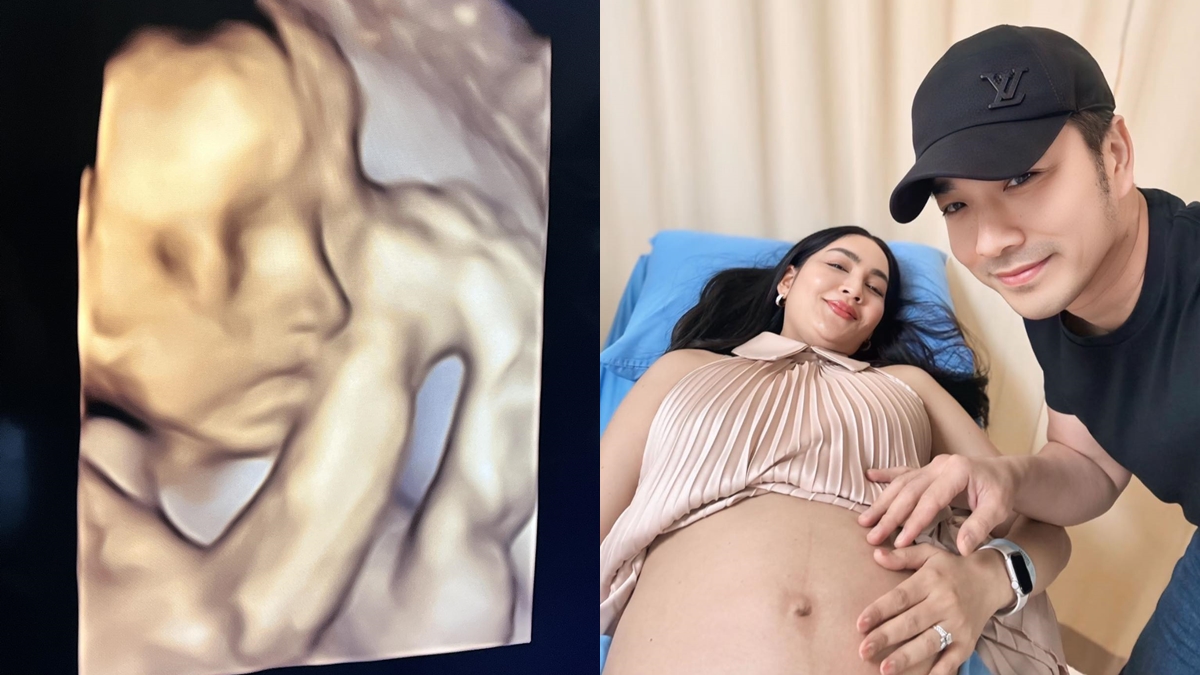

ด้าน “เจมส์ เรืองศักดิ์” ทำหน้าที่ดูแลภรรยาและลูกน้อยในครรภ์ไม่ห่าง พร้อมโพสต์ข้อความผ่านโซเซียลมีเดียว่าอบ “องครักษ์พิทักษ์คนท้อง” และ “ช่วงเวลาอันแสนพิเศษของครอบครัวเรา” ควบคู่กับภาพอัลตราซาวด์ที่เผยให้เห็นความละม้ายคล้ายคลึงของลูกสาวทั้งสองคน “น้องเมดา” และ “น้องมีเมตตา” สร้างรอยยิ้มและความประทับใจให้กับผู้ติดตามจำนวนมาก

นอกจากนี้ ครูก้อย ยังอัปเดตภาพอัลตราซาวด์ “น้องมีเมตตา” อายุครรภ์ 26 สัปดาห์ แบบอารมณ์ดีว่า ลูกสาวชอบเอามือบังหน้า ทำให้เห็นไม่ชัดสักที แต่แอบเห็นมุมข้างหน้าเรียว ๆ น้ำหนักตอนนี้กว่า 800 กรัม อยู่ในเกณฑ์มาตรฐาน ขณะที่น้ำหนักคุณแม่อยู่ที่ 69 กิโลกรัม และยังเพิ่มตามเกณฑ์เหมาะสม